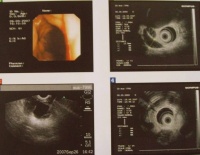

胆管癌超声内镜检查

的进行性黄疸食欲不振消瘦瘙痒等。如合并胆结石及胆道感染,可有发冷发热等,且有阵发性腹痛隐痛。如位于一侧肝管癌肿,开始常无症状,当影响至对侧肝管开口时,才出现阻塞性黄疸。如胆管中部癌不伴有胆石感染,多为无痛性进行性阻塞性黄疸。黄疸一般进展较快,不呈波动性。检查可见肝肿大、质硬、胆囊不肿大。如为胆总管下端部,则可扪及肿大的胆囊。如肿瘤破溃出血,可有黑便大便潜血试验阳性、贫血等表现。